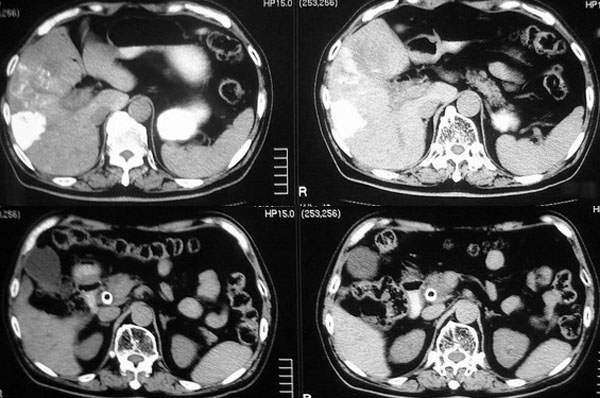

以下是引用逸风在2006-8-26 17:37:00的发言:[br]ct显示:\"壶腹癌肝转移\"行介入碘油栓塞术及胆总管内支架植入术后,肝右叶斑片状高密度碘油弥散,肝左叶见多个结节样低密度病灶,边缘清晰,肝左叶肝内胆管内气体影聚集.胆总管通常,腹膜后未见明显淋巴结肿大,片内所见其他未见明显异常.[br]诊断:1.壶腹癌肝转移\"行介入碘油栓塞术及胆总管内支架植入术后改变;2.肝左叶转移瘤,请与原片对比观察.